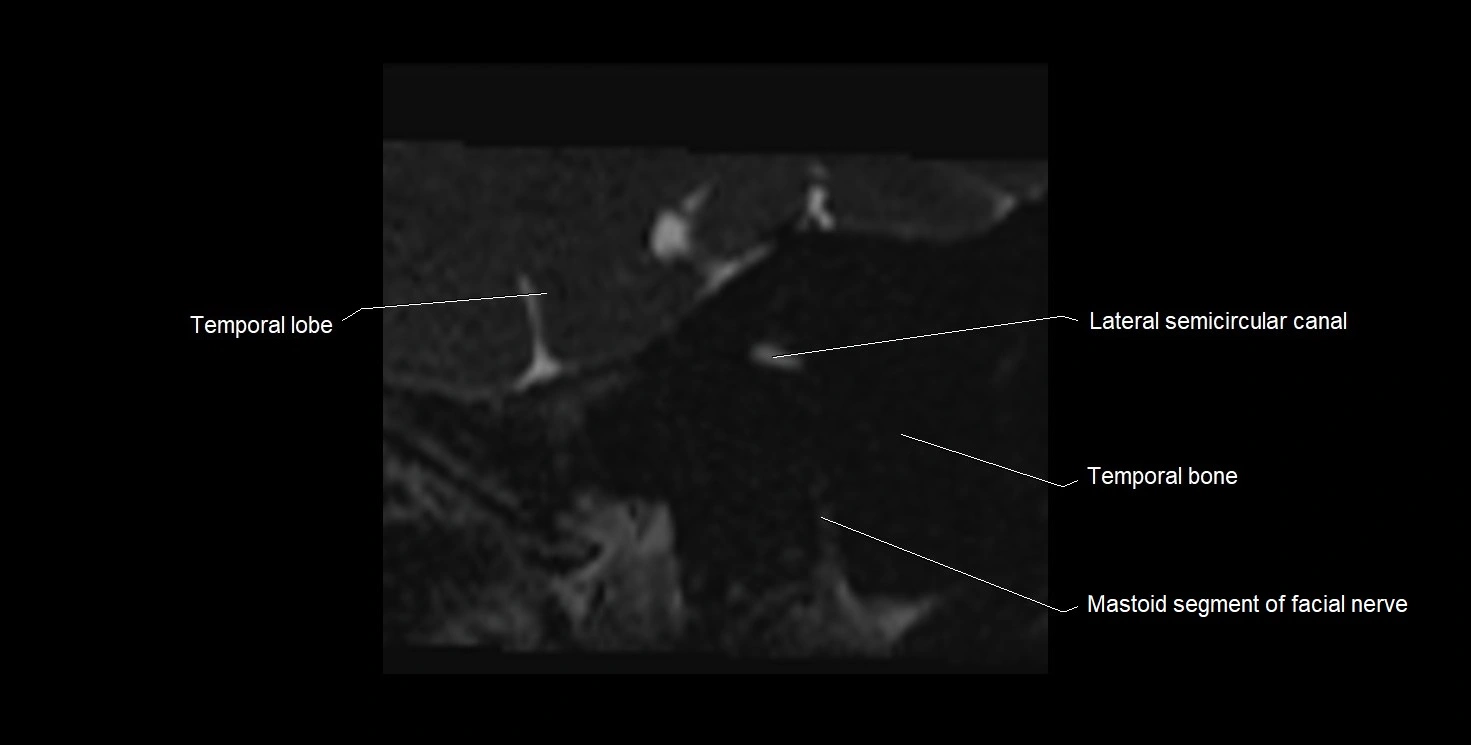

MRI Appearance

• The abducens nerve is a small, thin, linear structure

• Best visualized on high-resolution T2-weighted 3D MRI sequences (e.g., FIESTA or CISS)

• Seen as a hypointense (dark) line running from the brainstem at the pontomedullary junction, traversing the prepontine cistern, and entering Dorello’s canal under the petrosphenoidal ligament, then into the cavernous sinus, and finally the orbit

• May be challenging to visualize in standard MRI due to its small size

• Pathology may be inferred by absence, displacement, or enhancement of the nerve